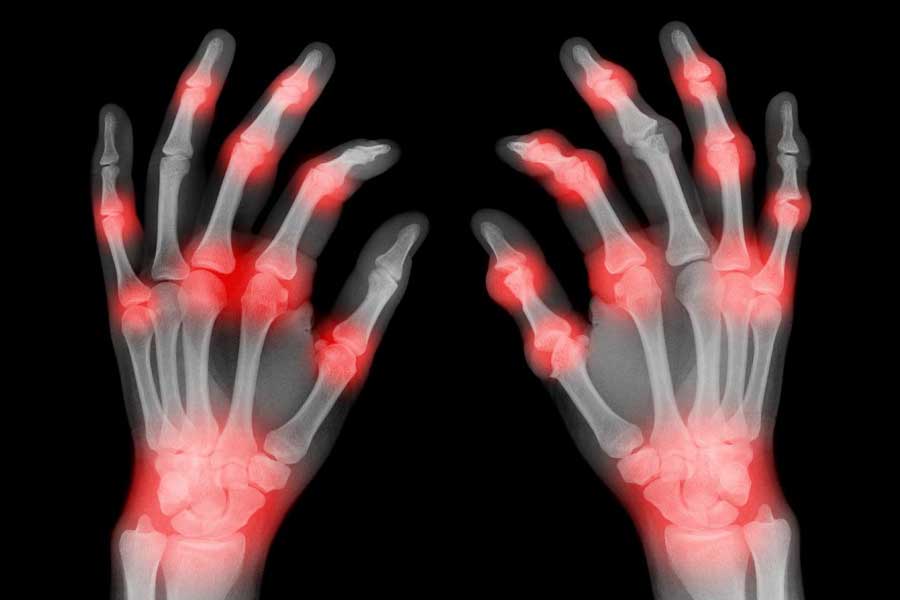

If you or someone you know suffers from Arthritis, a debilitating, painful disease, you know how much it can reduce quality of life. Painful, swollen and inflamed joints are the hallmark symptoms that present mostly on weight-bearing joints but can affect almost any part of your body. Arthritis can also affect anybody at any age, even children, but is mostly considered a disease of our older generation as it becomes more prevalent with increasing age.

is an auto-immune condition affecting 3x more women than men, and usually presents between the ages of 20-55. This inflammatory condition occurs when the body’s immune system incorrectly attacks the cells around the joints resulting in pain and swelling affecting mostly the hands, feet and wrists. With continued swelling the joint capsule is unable to hold the correct position leading to joint instability and damage. Whole-body inflammation (where other body systems are affected with inflammation) contributes to the pain, stiffness and fatigue found in those with RA. Quality of life is reduced as symptoms make doing daily activities difficult.